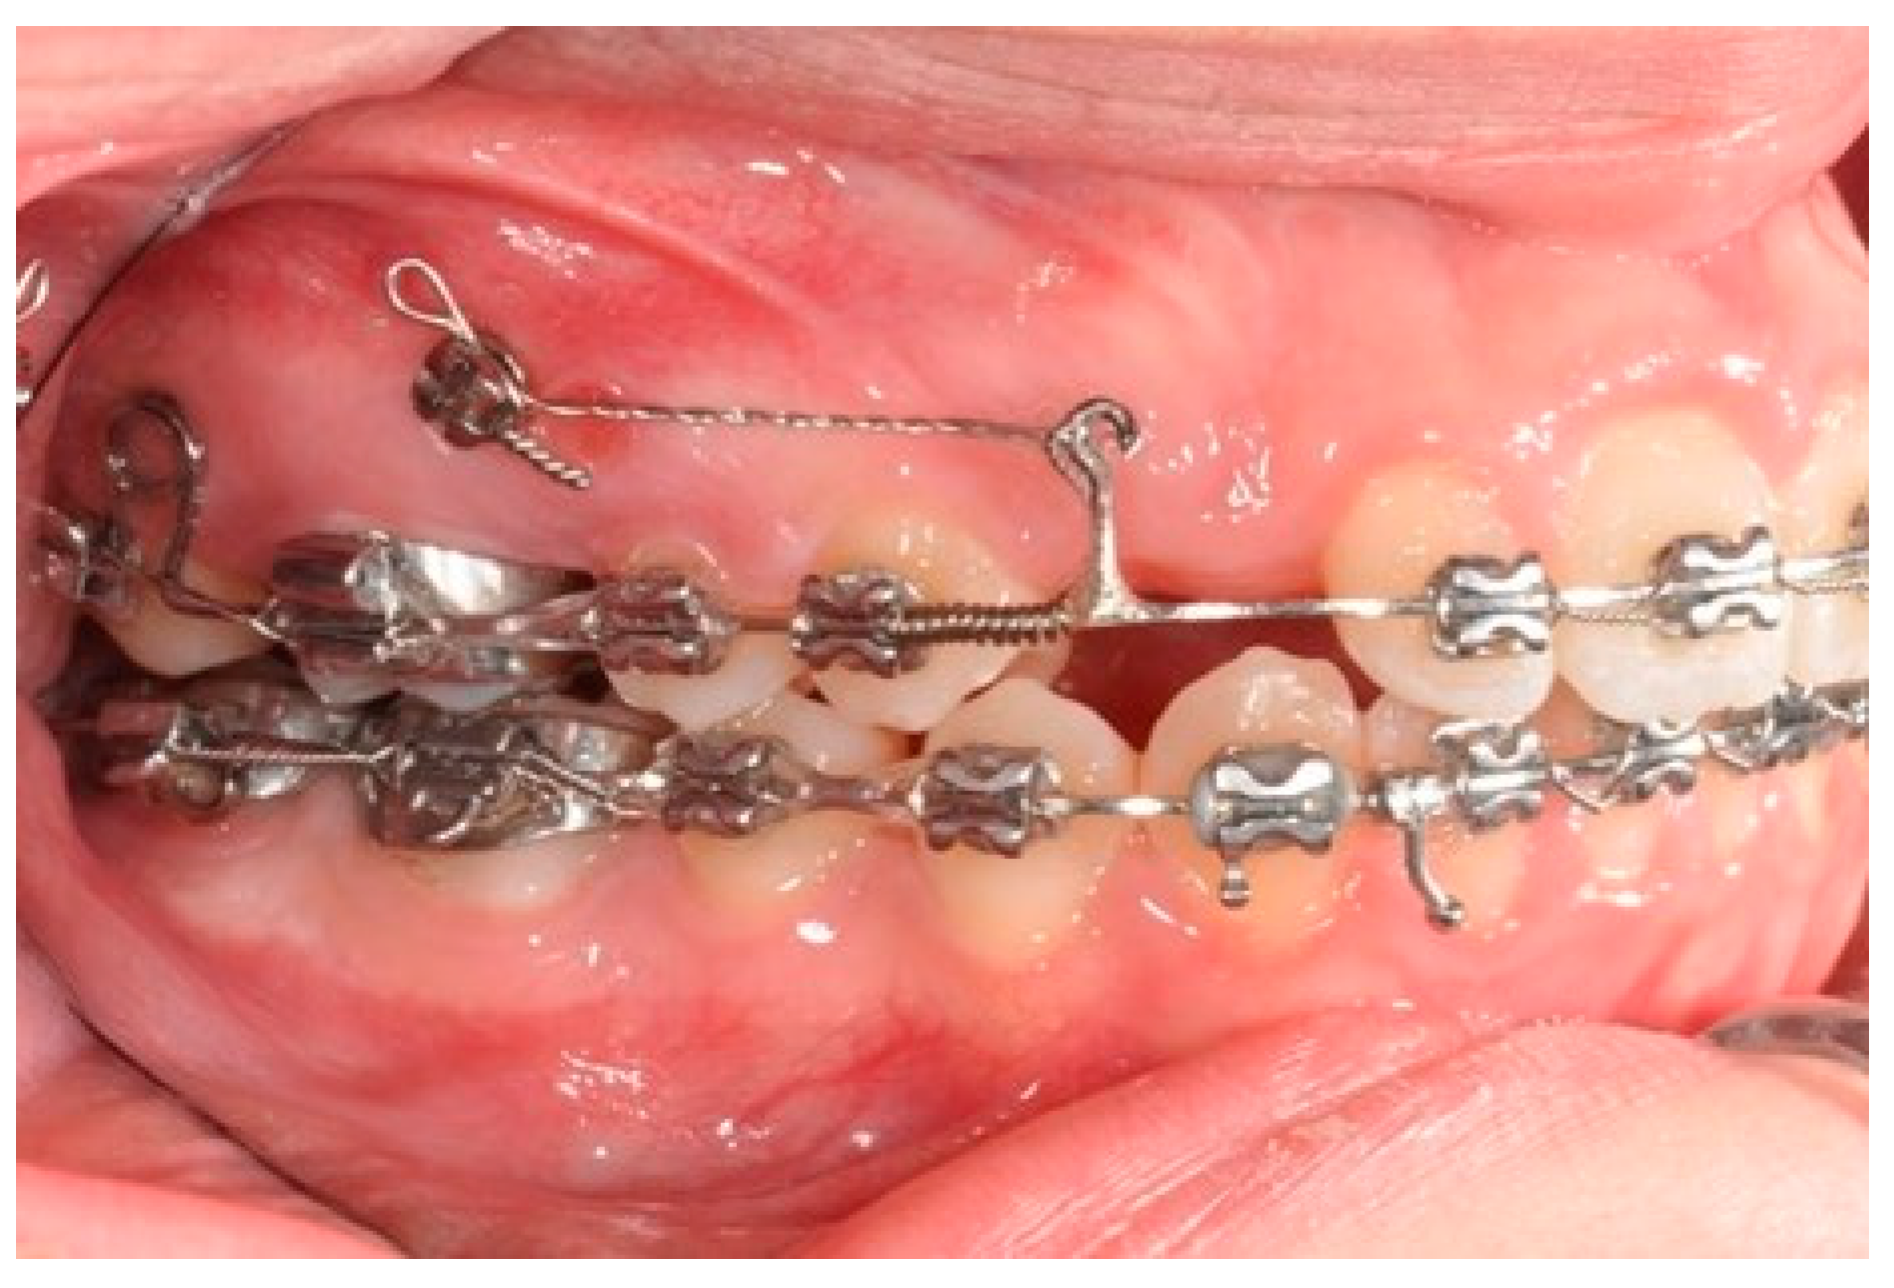

Figure 4. Molar and premolar distalization strategy.

After achieving the full bonding on the upper arch, two miniscrews (tads) are placed between the upper first molars and the second bicuspid, bilaterally. A 0.19 × 0.25 SS wire is shaped, adding a helical bulbous loop, bent lingually, flush to the second molar tube. At the same time, an active 7° lingual crown torque is placed on the second molar. A long spur with a mesial hook, just mesial to the bracket of the second bicuspid, is soldered. A metallic ligature is placed between the tads and the spurs.

The helical bulbous loop produces space distally to the upper first molars. An open coil is added between the second bicuspid and the first molar in order to move to the distal second and first molar at the same time (Figure 4 and Figure 5). Eventually, an elastic module is placed between the hooks on the second molars and the first molars in order to finish the combined distalization of the upper first molars.